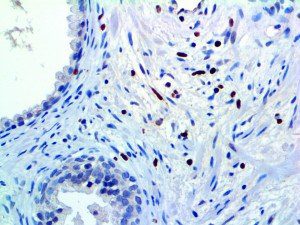

It is the ICU physician who is most likely to witness one of the deadliest manifestations of the abnormal immunological response, the cytokine storm syndrome (CSS). This response is also referred to by some as the cytokine release syndrome (CRS). CSS is characterized by continuous activation and expansion of macrophage and lymphocyte populations, which secrete large amounts of cytokines, causing the cytokine storm. This massive cytokine release is akin to hemophagocytic lymphohistiocytosis (HLH) disease, a syndrome characterized by initial unchecked and persistent activation of cytotoxic T lymphocytes and NK cells.

Clinical and laboratory manifestations of HLH include fever, enlarged liver and/or spleen, neurologic dysfunction, coagulopathy, liver dysfunction, cytopenias (i.e., low levels of erythrocytes, leukocytes, and/or platelets), hypertriglyceridemia, hyperferritinemia, hemophagocytosis, and eventually diminished NK cell activity as the immune system becomes progressively paralyzed. HLH can be familial (primary HLH) or secondary to another disease process (sHLH), such as rheumatic disease, in which it is referred to as macrophage activation syndrome (MAS, characterized by elevated ferritin).

This activation induces inflammatory monocytes to highly express IL-6, starting a localized and then systemic cascade effect that results in hyperproduction of IL-6, which accelerates the inflammatory process. Because IL-6 also increases vascular permeability, excessive levels cause blood vessels to become very leaky. This, along with clotting factors released from vascular endothelial cells, stimulates the coagulation cascade, resulting in microthrombosis (tiny clots), which leads to ischemia and tissue death of the kidney, intestines, heart, liver, brain and extremities.